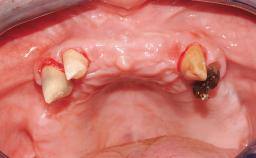

A 63-year-old female patient was referred to the University Medical Center in Groningen, Netherlands, for dental implant treatment. The patient had been edentulous in the upper jaw for 20 years. The remaining teeth in the lower jar had been removed two years before the consultation. The patient was wearing her first maxillary denture and her second mandibular denture; the latter was 1 year old at the time. The conventional upper denture had functioned satisfactorily for many years, but the patient complained about reduced stability and insufficient retention of her lower conventional denture. Her medical history revealed no significant findings. The intraoral examination revealed minor resorption of the maxillary alveolar process and extreme resorption of the mandibular alveolar process.